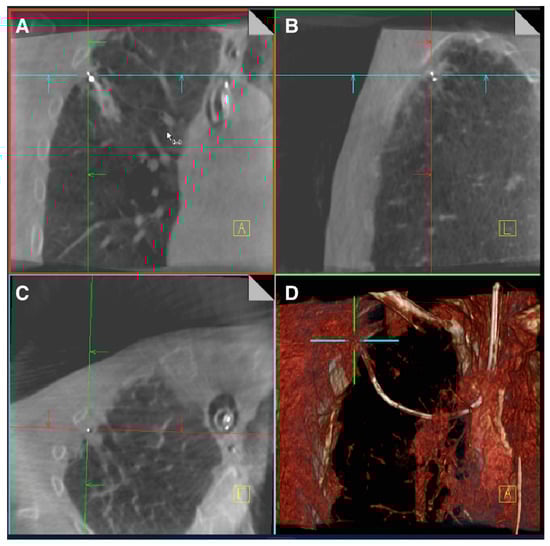

- Kalchiem-Dekel, O.; Fuentes, P.; Bott, M.J.; Beattie, J.A.; Lee, R.P.; Chawla, M.; Husta, B.C. Multiplanar 3D fluoroscopy redefines tool-lesion relationship during robotic-assisted bronchoscopy. Respirology 2021, 26, 120–123. [Google Scholar] [CrossRef]

- Reisenauer, J.; Duke, J.D.; Kern, R.; Fernandez-Bussy, S.; Edell, E. Combining Shape-Sensing Robotic Bronchoscopy with Mobile Three-Dimensional Imaging to Verify Tool-in-Lesion and Overcome Divergence: A Pilot Study. Mayo Clin. Proc. Innov. Qual. Outcomes 2022, 6, 177–185. [Google Scholar] [CrossRef]